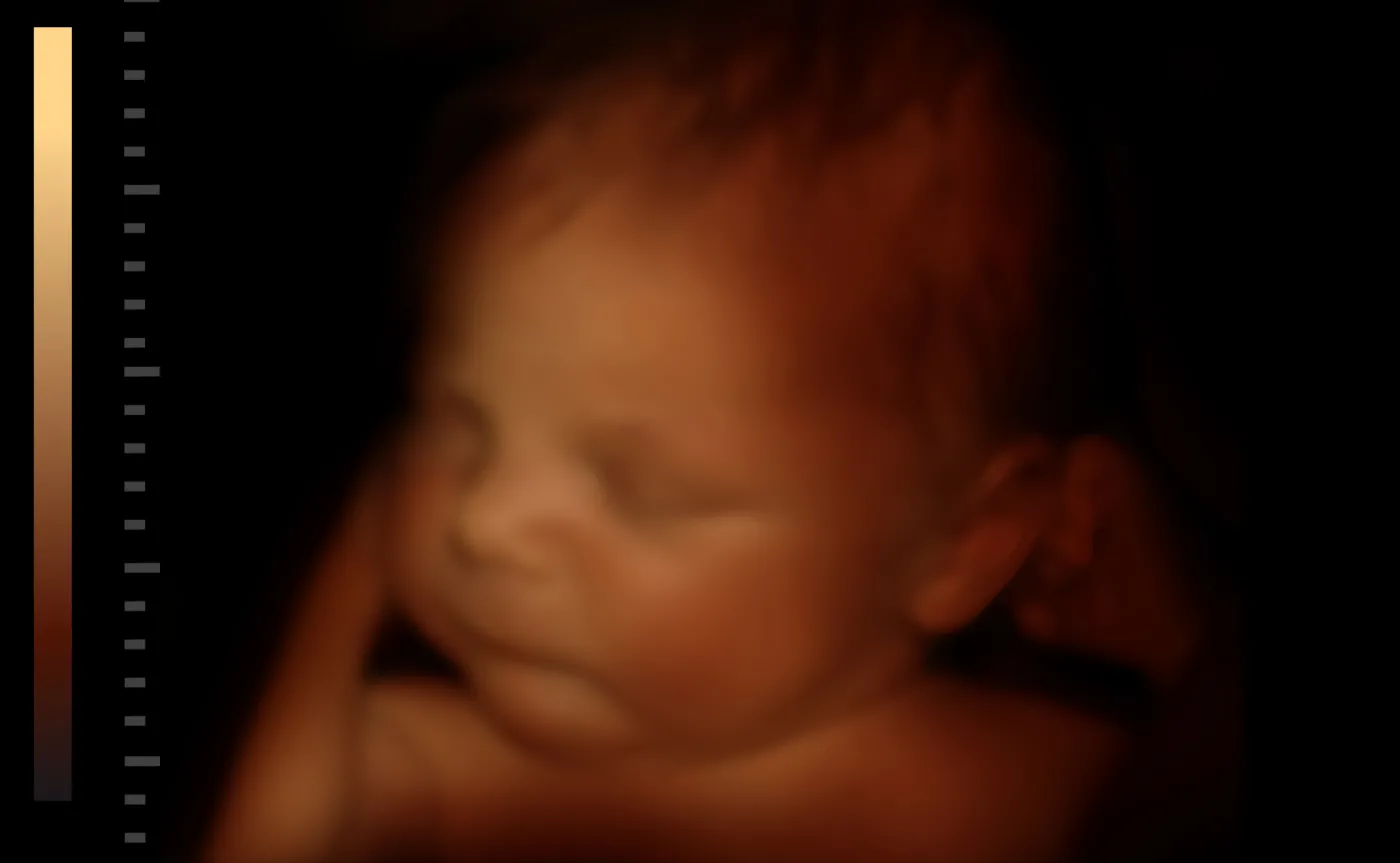

Badanie ultrasonograficzne (USG) – najpowszechniejsze wśród badań prenatalnych, wykonywane wielokrotnie w przebiegu ciąży w celu rozpoznania ewentualnych wad, niedojrzałości płodu oraz innych zaburzeń wewnątrzmacicznych. Pozwala na określenie wieku ciążowego, kosmówkowości w ciąży mnogiej, umożliwia ocenę dobrostanu płodu, diagnostykę ewentualnych wad płodu czy innych nieprawidłowości wewnątrzmacicznych. Obecnie coraz częstszym standardem są badania USG metodą 3D i 4D – taka technologia pozwala na jeszcze dokładniejsze śledzenie rozwoju dziecka m.in. budowy jego organów, ocenę łożyska, pomiar wielkości płodu, śledzenie jego ruchów.

- Diagnostyka prenatalna to element działań profilaktycznych. Wiele kobiet obawia się tego typu badań, często niesłusznie, ponieważ nowoczesne metody i testy diagnostyczne są bardzo precyzyjne i obarczone niewielkim ryzykiem powikłań. Wyspecjalizowane laboratoria genetyczne zapewniają dostęp do szybkiej i pewnej diagnostyki. Przykładem rozwoju medycyny w tym zakresie są również nieinwazyjne, bardzo czułe badania biochemiczne krwi czy technologia 4D stosowana w USG, która już w I trymestrze ciąży pozwala bardzo szczegółowo ocenić rozwój anatomiczny dziecka m.in. naczynia krwionośne. Warto, by kobiety nie rezygnowały z możliwości, jakie oferuje współczesna diagnostyka w tym zakresie – mówi ginekolog.